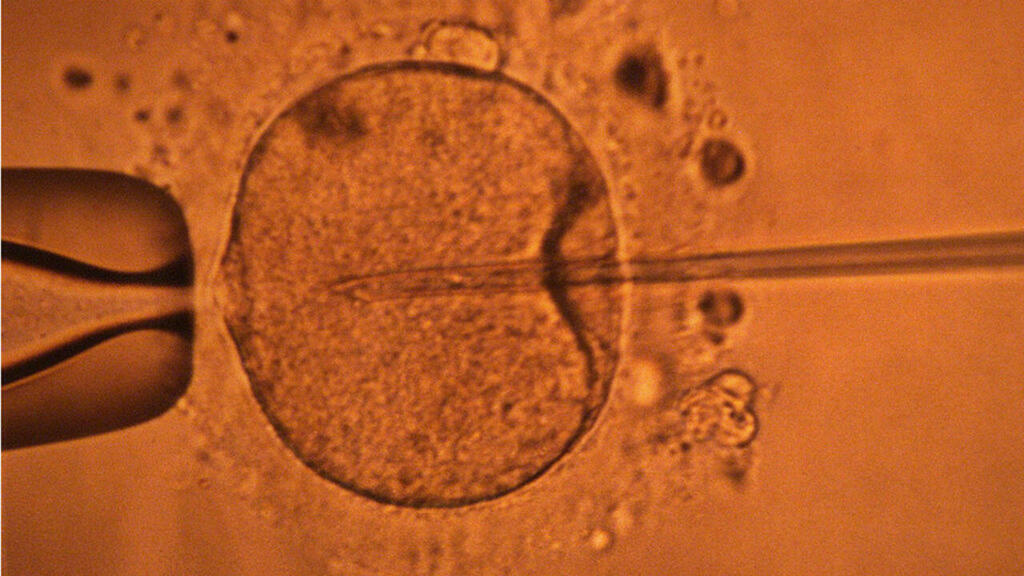

دراسة جديدة تكشف أن عمر الأب يؤثر على نتائج الحمل

كشفت دراسة جديدة أن عمر الأب يمكن أن يؤثر على صحة الجنين. فكلما تقدم الرجل في السن، زادت فرص ظهور طفرات جينية ضارة في حيواناته المنوية، مما قد يؤثر على فرص الحمل وصحة الطفل.